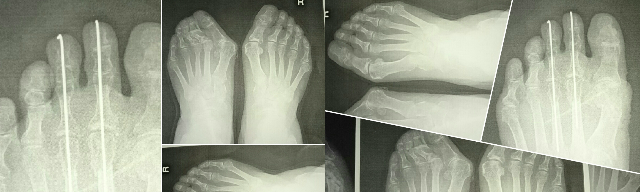

外反母趾、巻き爪、ハンマートゥ

リウマチ、膠原病、糖尿病、脳梗塞など

痛み、悩みに対処

原因を取り除く為に